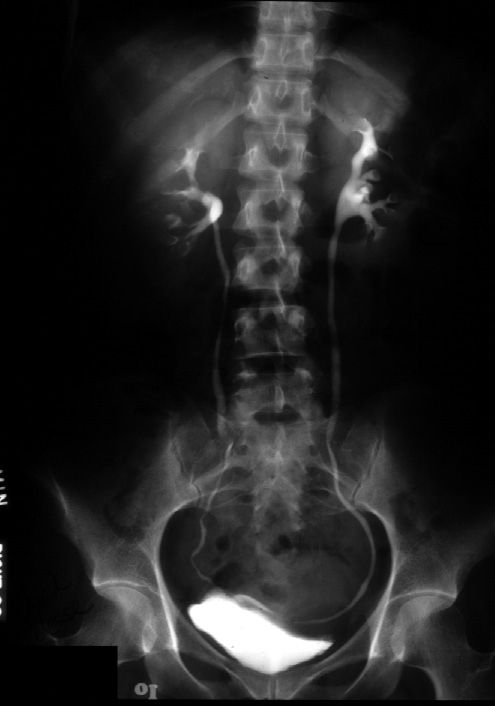

Note. This is a 10 minute film from an excretory urogram.

Identify -- renal contour, the calyces, the renal pelvis, the ureter, and

the bladder